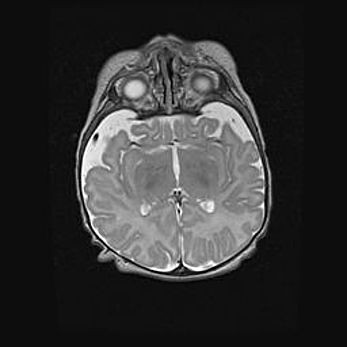

Наружная гидроцефалия с возможной атрофией височных областей.

Возраст: 28 дней

Вес: 3670 г

Пол: мужской

Окружность головы: 38 см

Срок гестации: 40 недель

Гидроцефалия головного мозга у новорожденных – это заболевание, которое характеризуется скоплением избыточного количества спинномозговой жидкости в желудочковой системе головного мозга в результате затруднения её перемещения от места выработки к месту поглощения в кровеносную систему или вследствие нарушения абсорбции. При открытой наружной форме гидроцефалии у новорожденных расширяются и переполняются субарахноидные пространства.

При нормотензивных  формах,  которые,  как  правило,  являются  следствием  перенесенных ишемических  повреждений  паренхимы  мозга,  возможно  сочетание микроцефалии  с нормотензивной гидроцефалией. В основе данных изменений лежит атрофия больших полушарий с преимущественной  локализацией  в  лобно-височных  областях.